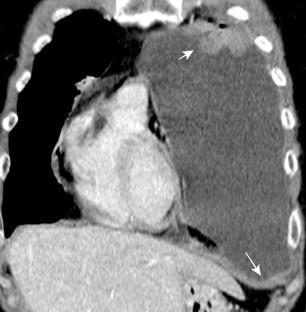

Marzo 2014: Perforación longitudinal distal secundaria a episodio de vómito (síndrome de Boerhaave). Derrame pleural izdo. que evoluciona a empiema.

Wang C-T et al. Tension hydropneumothorax in a Boerhaave syndrome patient: A case report . World J Emerg Med, 2021. Katabathina V et al. Nonvascular, nontraumatic mediastinal emergencies in adults:a comprehensive review of imaging findings. Radiographics. 2011.